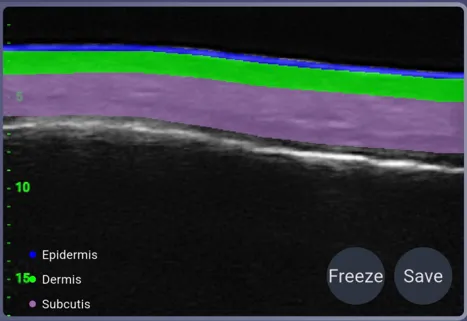

AI-Powered Organ Auto-Identification

Aesthetic Structure Visualization